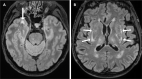

Figure 4

Axial T2 FLAIR brain MRI of two subjects with a pathogenic NOTCH3 variant in UK Biobank. (A) A woman in her 50s, carrying a p.Arg1231Cys variant that affects EGFR domain 31, with WMH involving the right anterior temporal lobe (arrow). (B) A man in his 60s, carrying a p.Arg578Cys variant that affects EGFR domain 14, with WMH involving the external capsule bilaterally (arrows). EGFR, epidermal growth factor-like repeat; FLAIR, fluid attenuated inversion recovery; WMH, white matter hyperintensity.